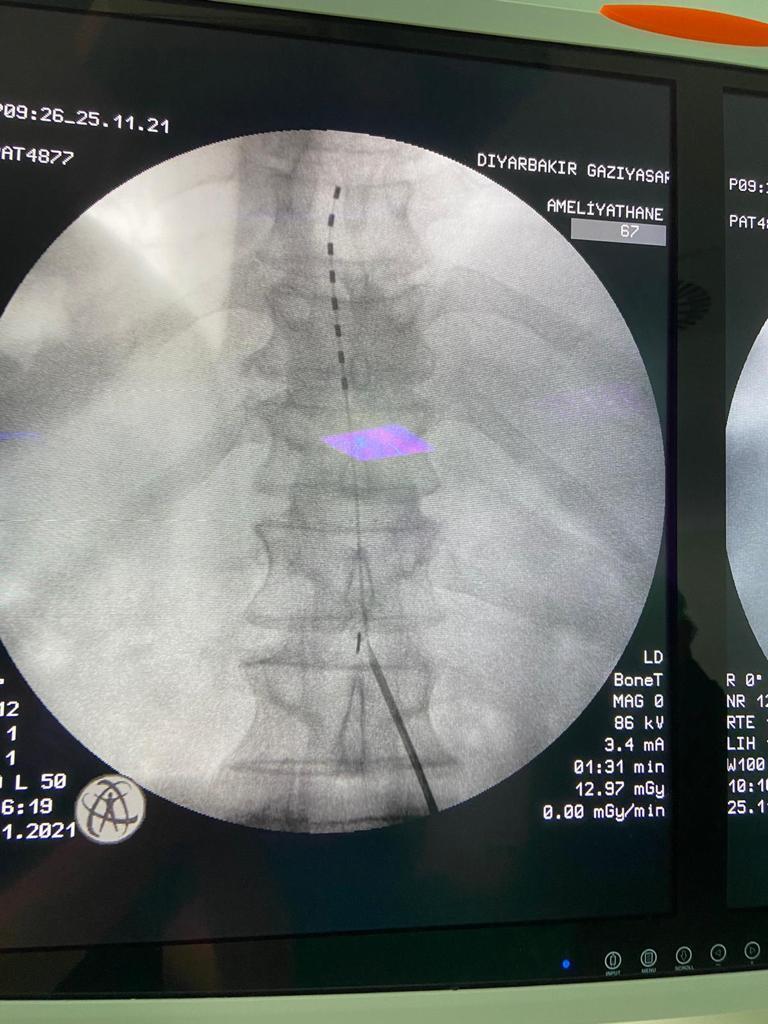

Terör mağduruna, 27 yıldır dinmeyen ağrıları nedeniyle 'ağrı pili' takıldı

Şırnak'ta, 1994 yılında terör örgütünün yola döşediği mayının patlaması sonucu sol bacağını diz altından kaybeden İbrahim Karahan'a (69), 27 yıldır geçmeyen ağrısı için omuriliğine 'ağrı pili' takıldı. Ameliyatı gerçekleştiren doktorlardan Gazi Yaşargil Eğitim ve Araştırma Hastanesi Algoloji Uzmanı Fahrettin Kırçiçek, hastaya ağrı pili takıldığını belirterek, "Çok büyük olasılıkla fayda göreceğini düşünüyoruz. Şu an geçici pil aşamasındayız. Hastamızın gördüğü faydaya göre yaklaşık 10 gün sonra kalıcı pile geçeceğiz" dedi.

Farklı illerde çeşitli hastanelere başvuran ancak ağrısı bir türlü dinmeyen Karahan, son olarak Diyarbakır Gazi Yaşargil Eğitim ve Araştırma Hastanesi'ne başvurdu. Hastanın durumunu değerlendiren doktorlar, hastaya ağrı pili takılmasına karar verdi. Bir saat süren başarılı ameliyatın ardından hastaya 'ağrı pili' takıldı.

Ameliyatı gerçekleştiren doktorlardan Algoloji Uzmanı Fahrettin Kırçiçek, önce geçici ağrı pili taktıklarını, sonuç almaları durumunda 10 gün sonra kalıcı ağrı pili takacaklarını ifade ederek şöyle konuştu:

"Hastamız Şırnak'tan bizim polikliniğimize başvurdu. Mayına basması sonucu sol diz altından ayağını kaybetmiş. Yüksek doz ilaç kullanmaktaydı. Bize başvurmasından sonra değerlendirmelerini yaptık. Önce algolojik bazı girişimler uyguladık. Yanıt alamamamız üzerine hastaya ağrı pili uygulamaya karar verdik. Ağrı pili uygulaması ameliyathanede yaklaşık bir saat süren bir işlem. Başarısız bel cerrahisi dediğimiz geçmeyen bel ve bacak ağrılarında, damar tıkanıklığına bağrı ağrılarda ve bu şekilde fantom ekstermite tarzı dediğimiz kopma sonrası gelişen uzuvlardaki ağrılarda kullandığımız bir işlem. Hastamıza da bu işlemi uyguladık, çok büyük olasılıkla fayda göreceğini düşünüyoruz. Şu an geçici pil aşamasındayız, hastamızın gördüğü faydaya göre yaklaşık 10 gün sonra kalıcı pile geçeceğiz. Sonra da 20-25 yıl pilin üstünde kalmasını düşünüyoruz."